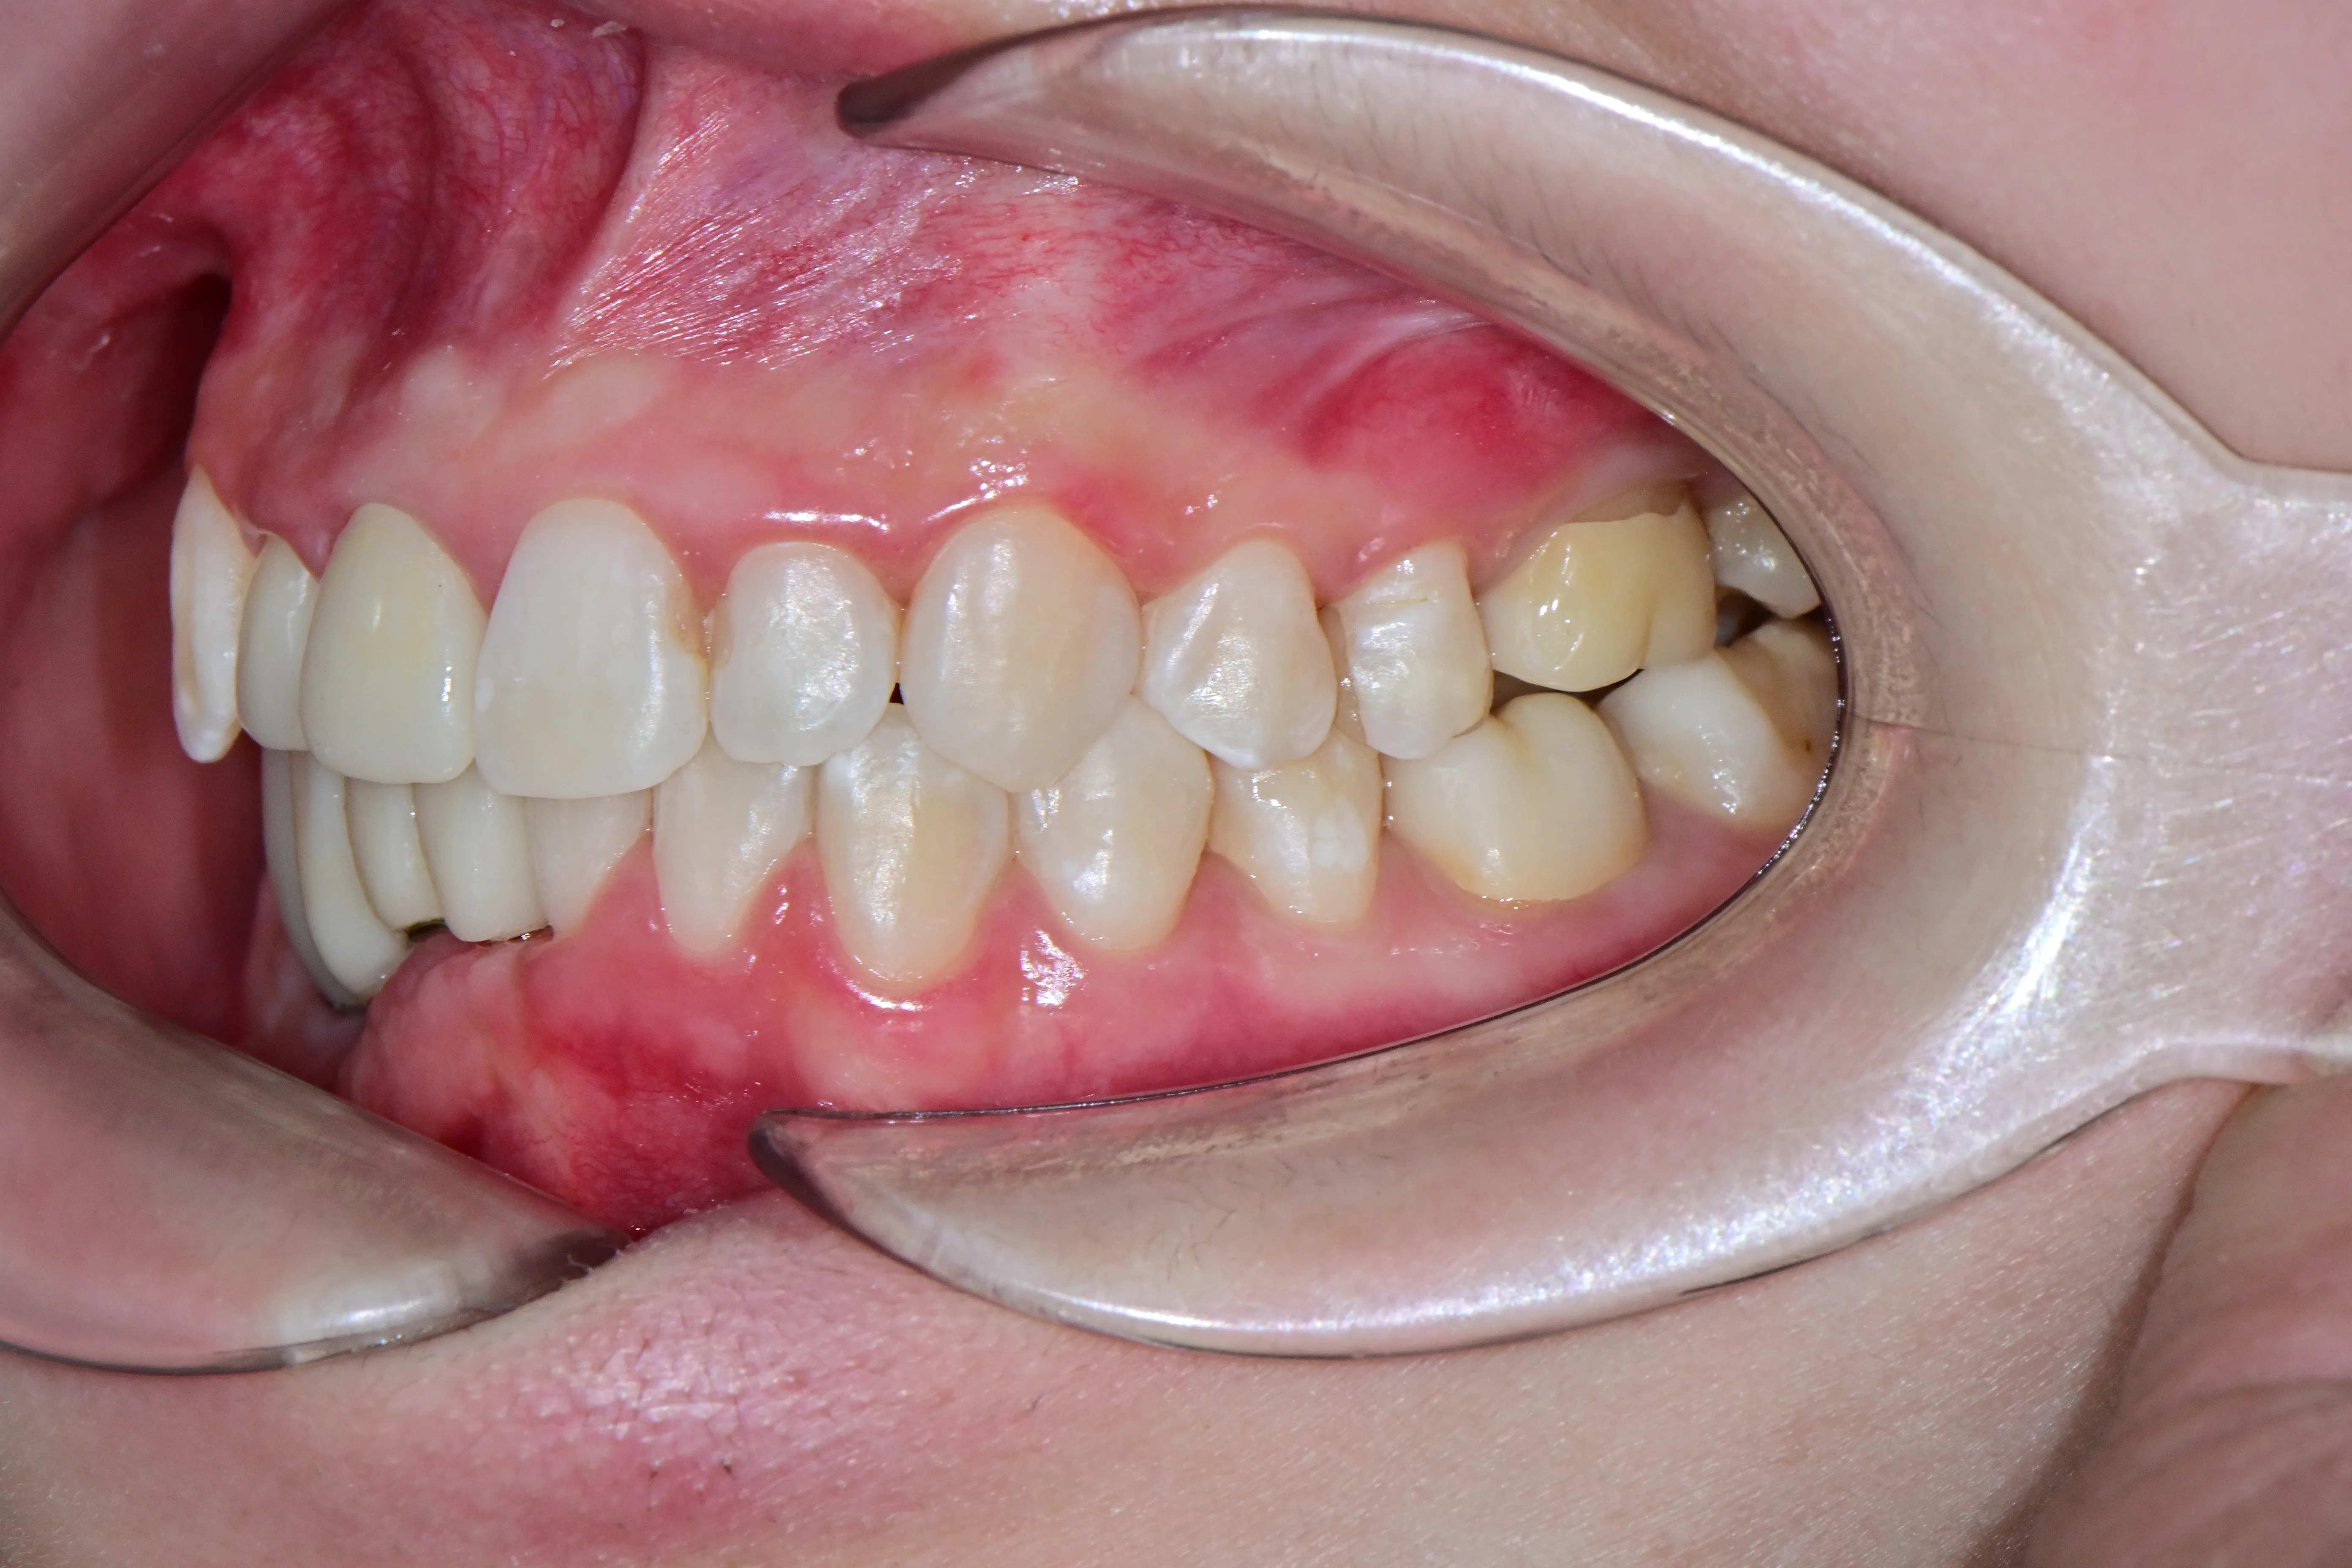

만 21세 환자로, 기존에 사고로 여러 치아를 다치고 상실한 상태로 매우 심한 교합무너짐이 있었습니다.

치료전 (Before)